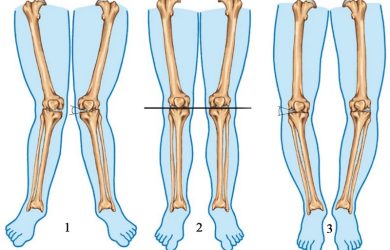

О-подібне викривлення ніг – стан, коли коліна розвернуті назовні та утворюють “колесо”, при зведених разом стопах Використовуючи наукову